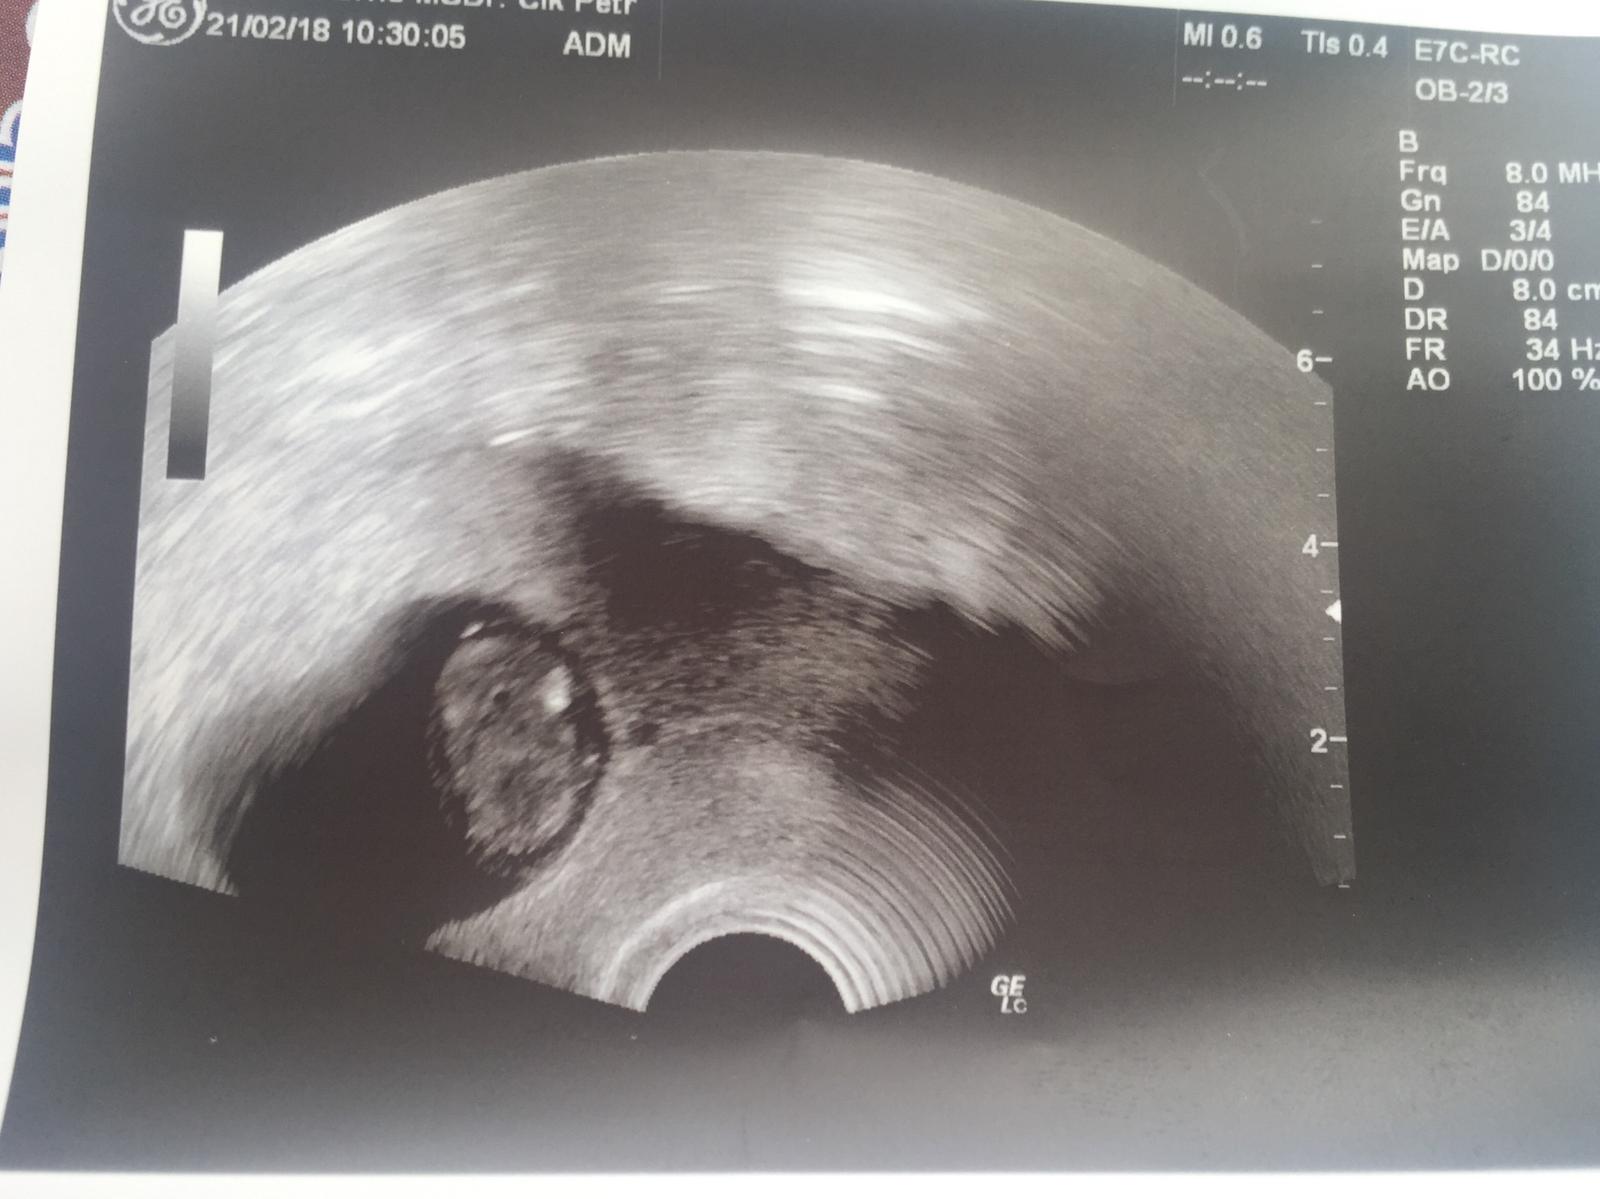

Ahojky tak uz mam po kontrole. Drme zkontroloval a pak oblecte se. Tak sem ho ukecala na utz sice mrmlal ale kdyz sem mu rekla ze minule to ve 13tydnu skoncilo tak pochopil. Zas byl dlouho ticho pak rika mimino tam je ale hledam sedicko a ve me uplne hrklo. Mam to na kazde kontrole ze sou dlouho ticho a pak tady je.... nakonec teda vse ok srdicko bije. Ma prstiky. Vypadalo trochu jak krtek. Na vaginalni utz prej uz je velky a pres bricho je jeste maly. Ale zkusil obe a prcka sem pekne videla. Asi spal pac se nehybal ale srdicko bylo videt tak snad ok. Nemeril ale ptala sem se jestli odpovida velikostne a prej jo. Dalsi kontrola uz u me dr za tri tydny.